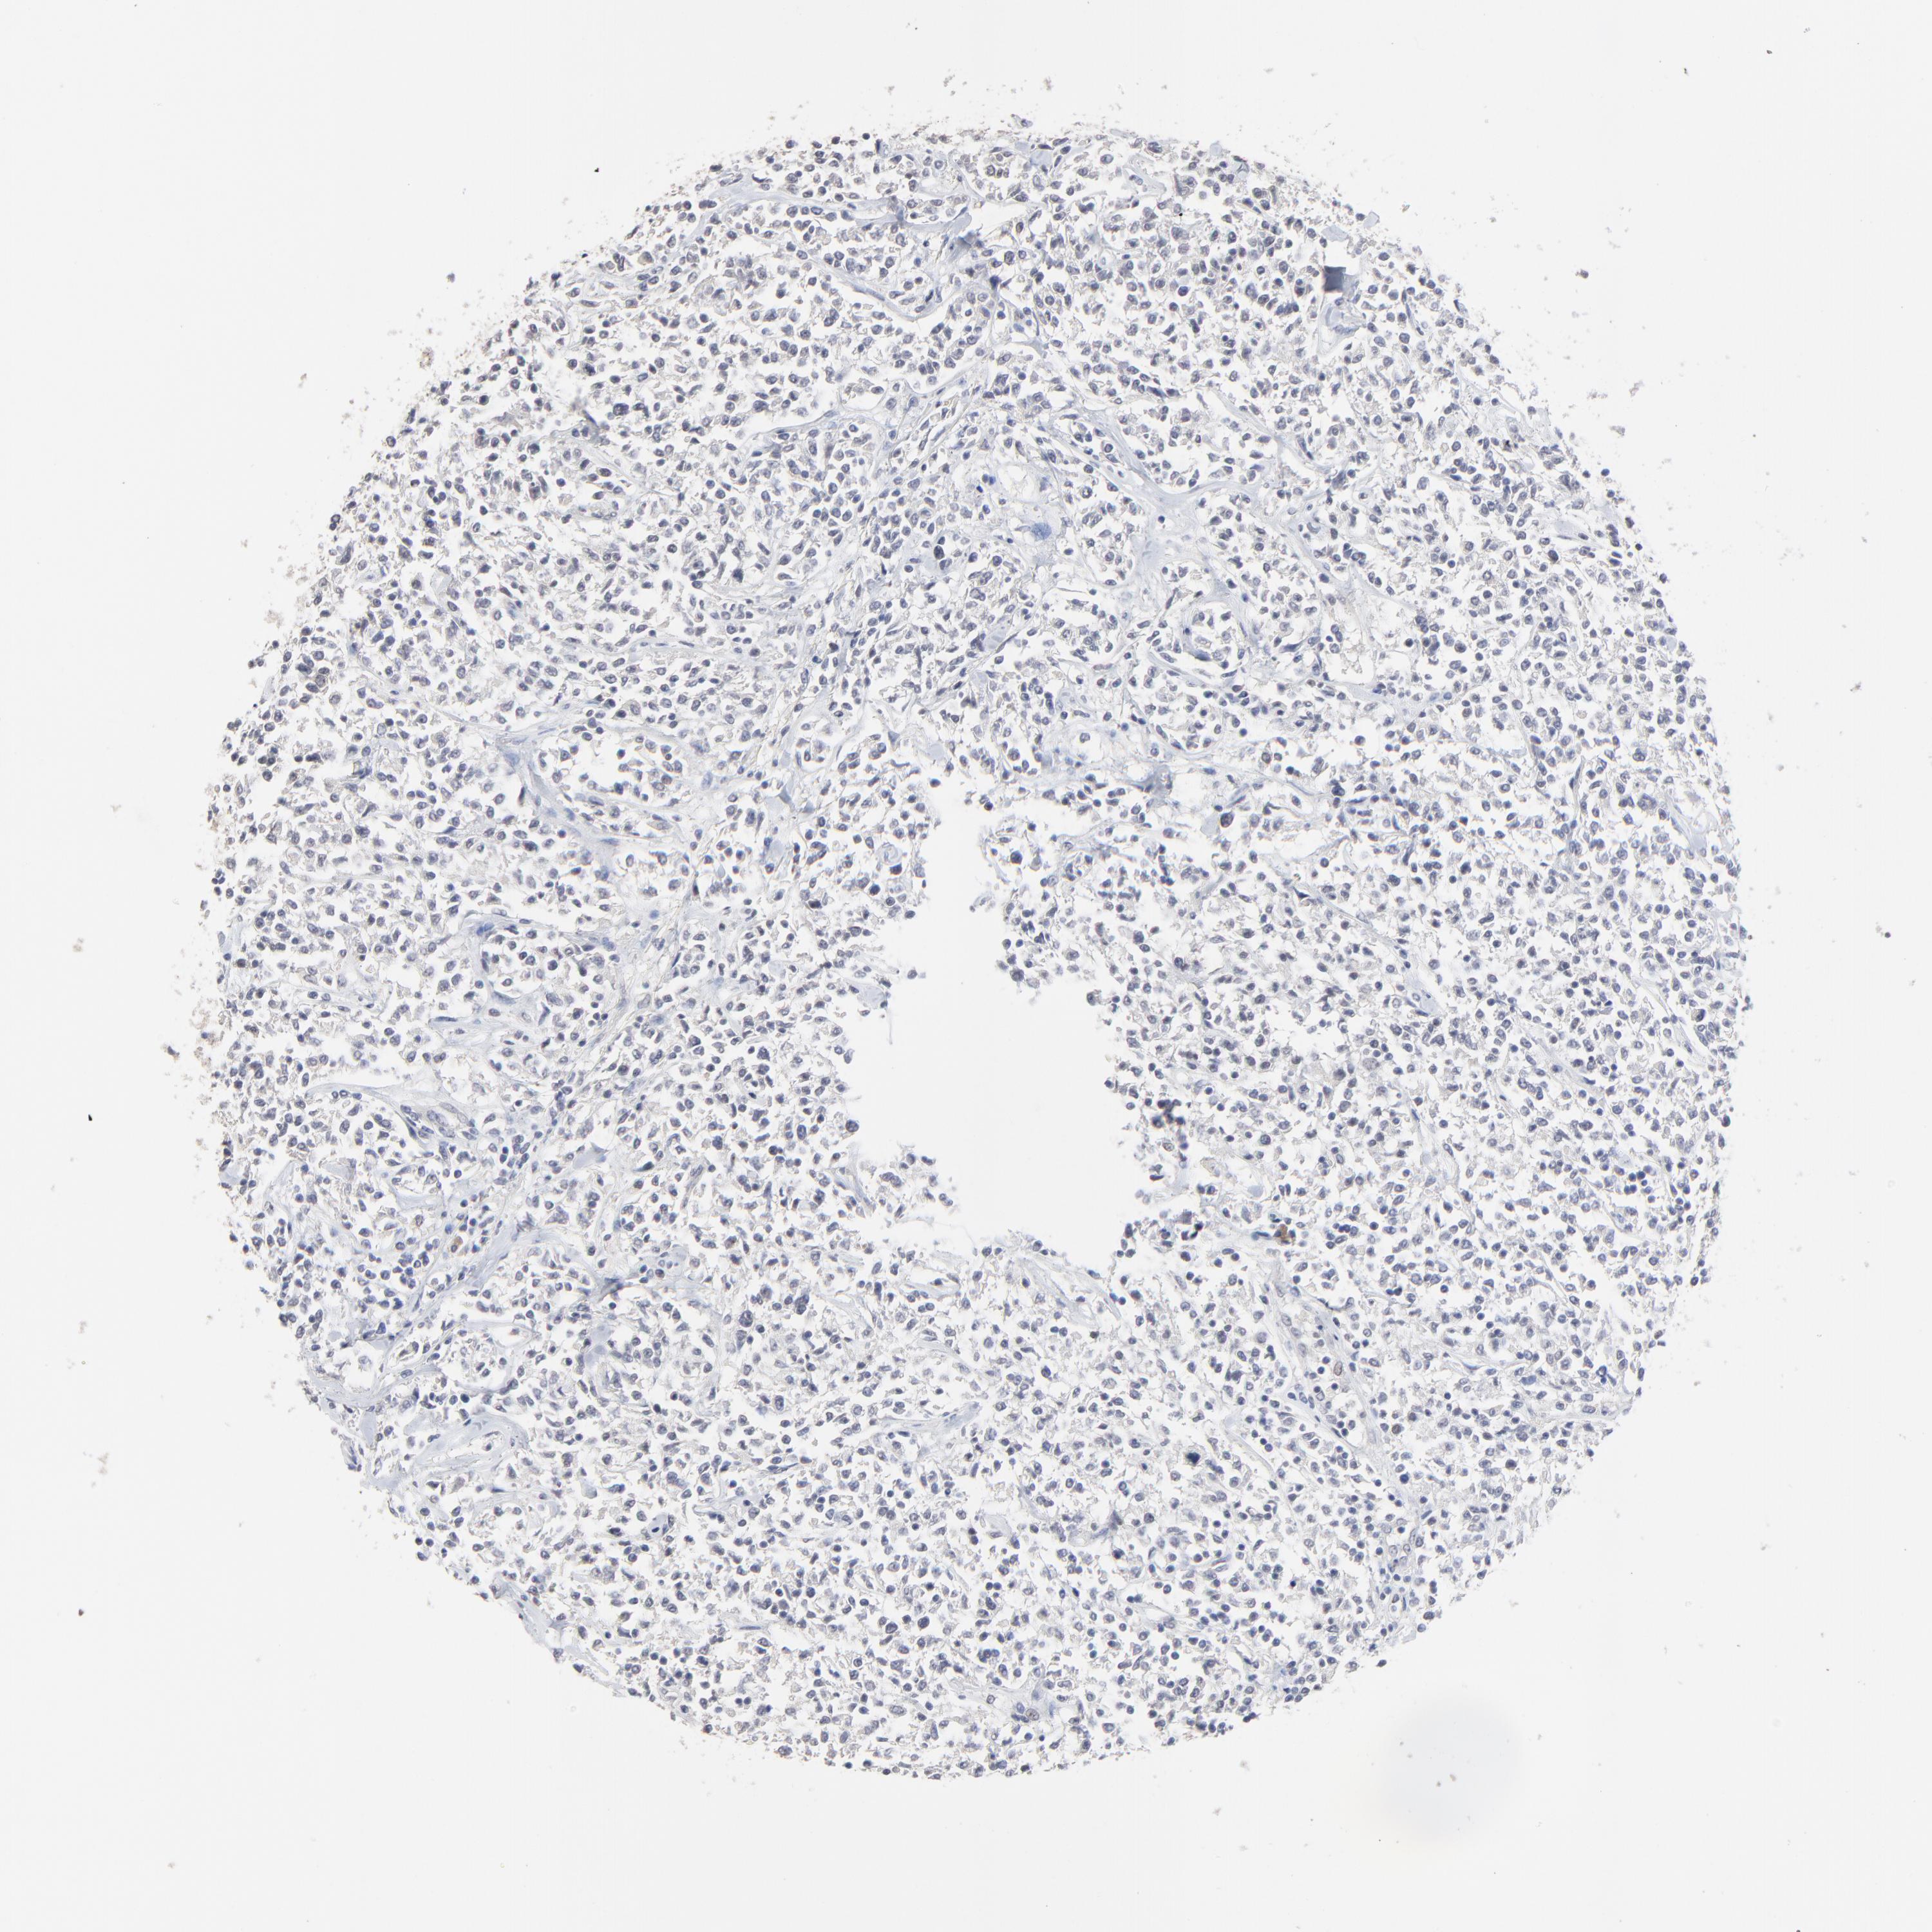

Antibody HPA003093

Staining

High

Medium

Low

Not detected

Intensity

Strong

Moderate

Weak

Negative

Quantity

>75%

75%-25%

<25%

None

Location

Nuclear

Cytoplasmic/membranous

Cytoplasmic/membranous,nuclear

Malignant lymphoma, non-Hodgkin's type, High grade

Hodgkin's disease, NOS

Malignant lymphoma, non-Hodgkin's type, Low grade